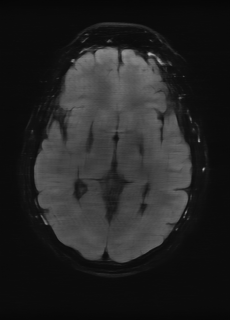

As we observe from the right image in Fig. 2, our BRM, both from MIMO and SISO settings, predicts the performance of dedicated models with a high correlation. We further choose the best three , and perform the last stage of fine-tuning accordingly to (6). A visual evaluation on real data is shown in Fig. 3. For simulated data, please refer to the Supplemental Material section.

Base on the best performing , we perceive that among , , and FLAIR, the results are best when is sampled the most. We suggest that this makes intuitive sense as images provide the best contrast out of the three sequences, which can compensate for the details lost in other images. The same observation can be made on the simulated data, where both and FLAIR show good contrast. When the time setting is changed to non-uniformity, we can see that our search for the best sampling strategy reflects the change. is sampled more as a result of faster acquisition time, while is still sufficiently sampled.

| Sequence | LR | SISO | MIMO | MIMO tuned | GT |

|---|---|---|---|---|---|

(a) 34.38/0.9371

(a) 34.38/0.9371

|

(b) 42.42/0.9883

(b) 42.42/0.9883

|

(c) 44.60/0.9920

(c) 44.60/0.9920

|

(d) 45.50/0.9940

(d) 45.50/0.9940

|

(e) PSNR/SSIM

(e) PSNR/SSIM

|

|

(f) 29.74/0.8903

(f) 29.74/0.8903

|

(g) 36.25/0.9734

(g) 36.25/0.9734

|

(h) 36.42/0.9752

(h) 36.42/0.9752

|

(i) 37.70/0.9832

(i) 37.70/0.9832

|

(j) PSNR/SSIM

(j) PSNR/SSIM

|

|

(k) 39.89/0.9311

(k) 39.89/0.9311

|

(l) 43.94/0.9864

(l) 43.94/0.9864

|

(m) 44.74/0.9883

(m) 44.74/0.9883

|

(n) 45.49/0.9894

(n) 45.49/0.9894

|

(o) PSNR/SSIM

(o) PSNR/SSIM

|